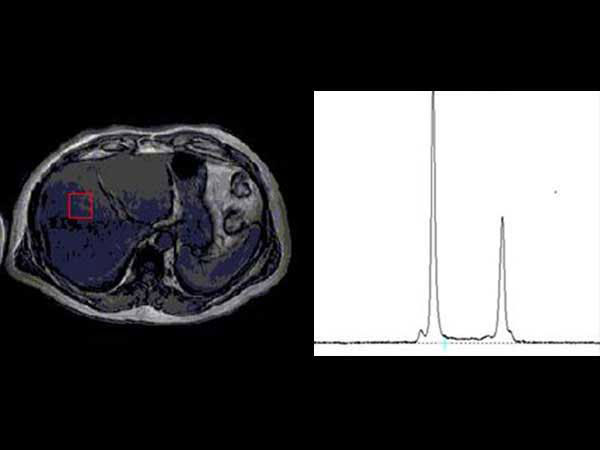

Advanced Liver MR - mDIXON Quant

University of Michigan Hospital, Ann Arbor, USA